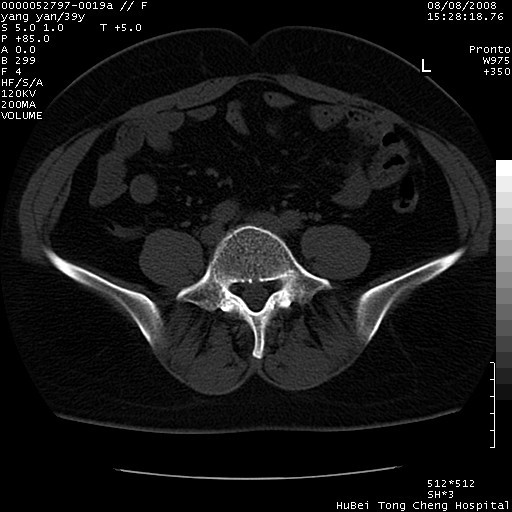

患者 女,39岁。因外伤检查,偶然发现。

典型!双侧骶髂关节致密性骨炎。

典型!病变主要累及双侧髂骨。常见于育龄期妇女。

致密性骨炎,一般不跨越关节面,可是这个骶骨关节面也有硬化。

髂骨致密性骨炎系一种以骨质硬化为特点的非特异性炎症,有高度致密的骨硬化现象,尤其以髂骨下2/3更为明显,但关节间隙则无改变。因位于骶髂关节,且该关节症状明显,故又称之为“骶髂关节致密性骨炎”。 本病90%以上为中年女性,以妊娠后期、尤其分娩后为多见,亦可见于尿路或女性附件慢性感染后,或盆腔内其他感染。此外,臀骶部的外伤亦可诱发或引起本病。  妊娠、分娩及外伤均可引起骶髂关节韧带的撕裂而易使局部的血供受阻。因此早期局部呈现充血、水肿及渗出增加等,渐而局部出现增生与变性反应,随着胶原纤维的致密化而向硬化演变;血管形成厚壁血管,易闭塞而引起髂骨耳状面处缺血和缺氧,骨质呈现硬化性改变,以致手术时局部出血较少。骶髂关节囊壁显示纤维增生、弹性降低及松动样改变。继发于盆腔内炎症者亦出现相类似的病理改变,可能系细菌内毒素作用所致。